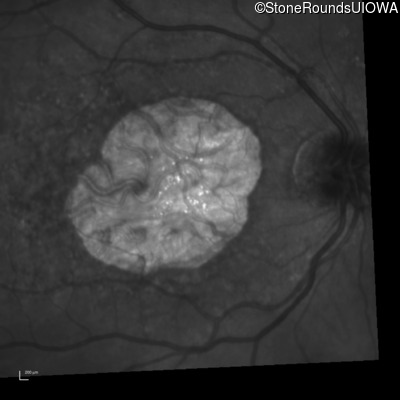

Infrared Fundus Photograph - Left - 20/125

Exemplar